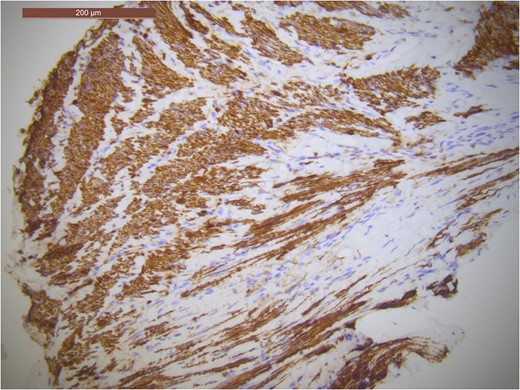

A CT guided fine needle aspirate (FNA) was carried out ~1 month after her initial surgery. Histopathology showed abnormal smooth muscle proliferation within lung parenchyma (Fig. 3). The smooth muscle cells were positive for smooth muscle Actin, Vimentin and Desmin protein (Fig. 4). This is suggestive of a smooth muscle tumour (which in the lung is most likely to be metastatic) or lymphangioleiomyomatosis. The immunohistochemistry favoured the diagnosis of a smooth muscle tumour.

Immuno-stain with brown staining indicating expression of desmin protein as seen in smooth muscle cells.